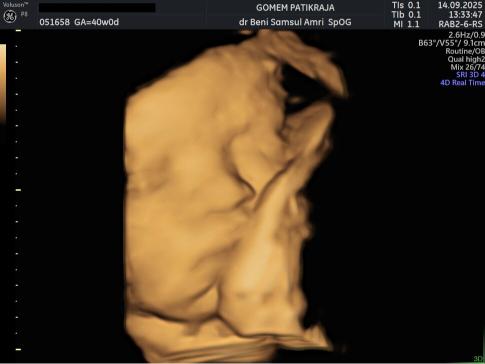

Gambaran Hasil USG Janin 41 Minggu